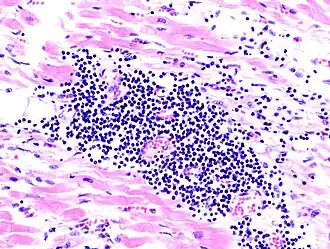

Microscopia de miocardite numa pessoa com insuficiência cardíaca aguda